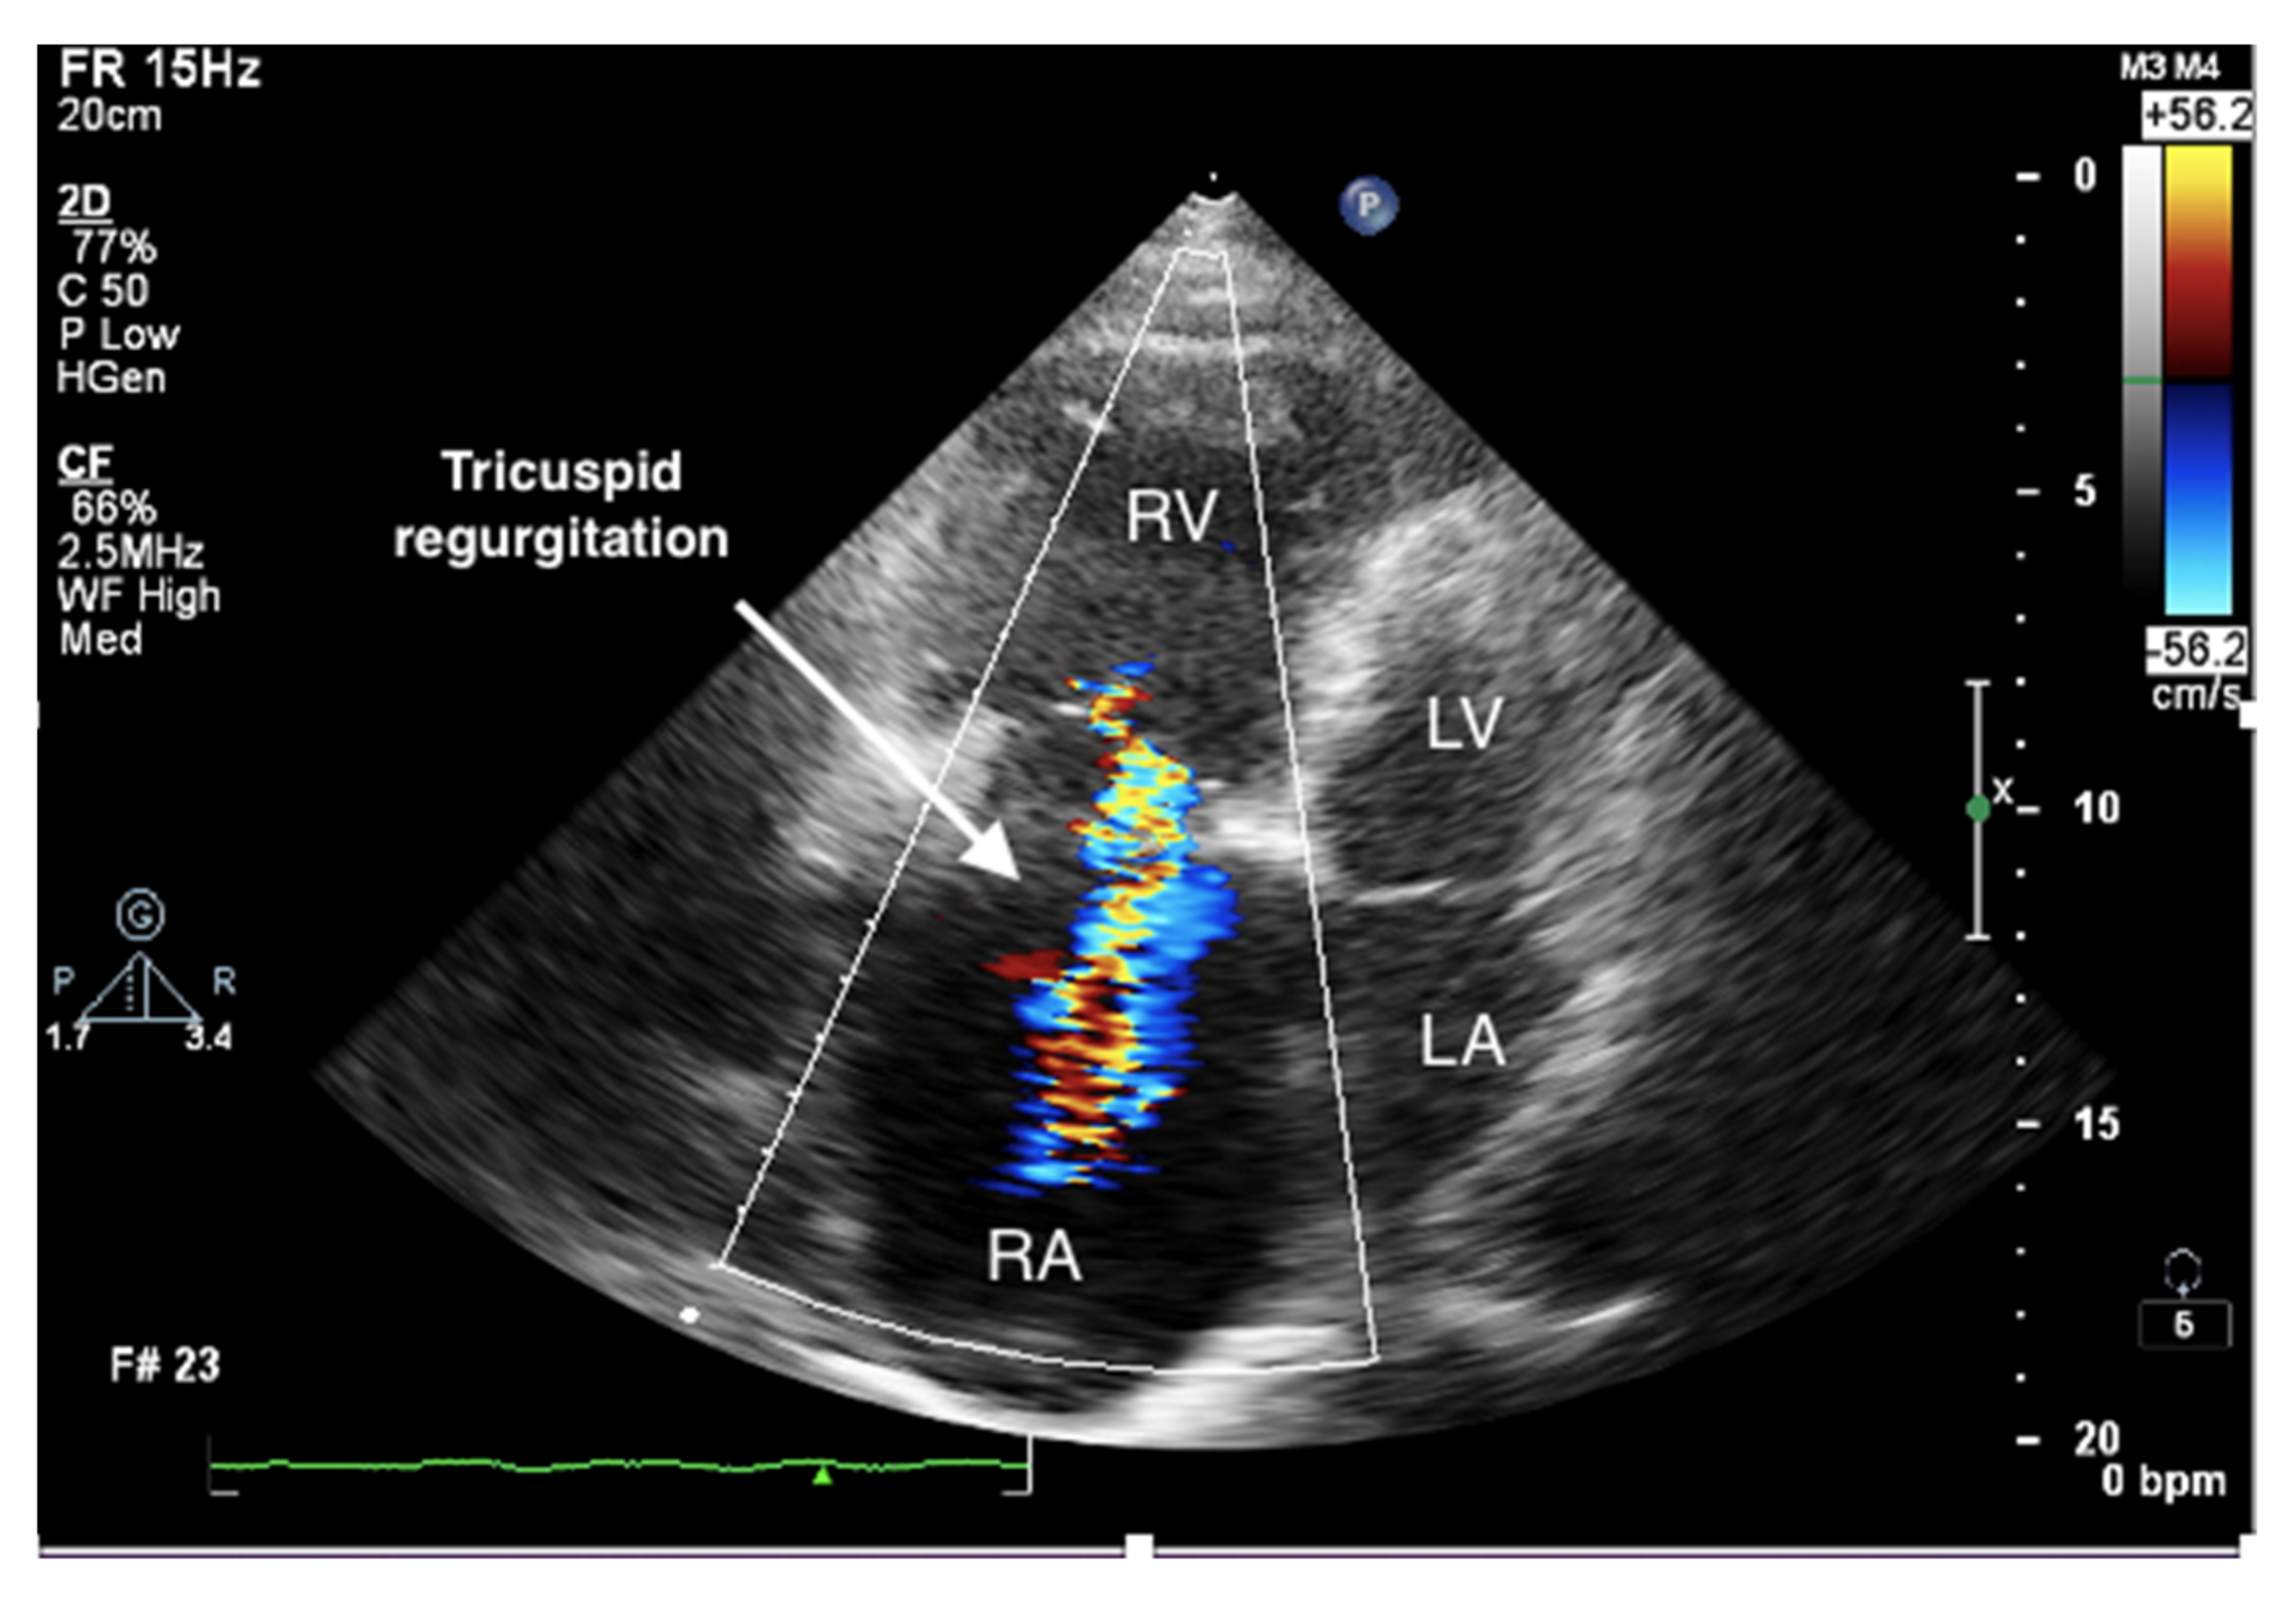

Figure 4.

Enlarged right ventricle and right atrium. Tricuspid regurgitation. 2D-TTE, RV-focused apical 4CH view.

It is believed that if there is no RV outflow tract stenosis, the right ventricular systolic pressure (RVSP) is equal to the pulmonary artery systolic pressure (PASP) [70]. In everyday practice, the calculation of PASP is based on a simplified Bernoulli equation applied to peak tricuspid regurgitation velocity (TRV). TRV should be measured in several views, aiming at the best image quality and maximum velocity in continuous-wave Doppler and avoiding excessive gain and artifacts (Figure 12 and Figure 13). According to the equation, PASP = 4 (TRV)2 + RAP [71,72]. In addition, based on the measurements of end-diastolic pulmonary regurgitant return wave velocity (PRVend), it is possible to estimate pulmonary artery diastolic pressure (PADP) using the PADP = 4 (PRVend)2 + RAP formula [73]. On the other hand, PASP and PADP values can be used to calculate approximations of mean pulmonary artery pressure (mPAP) using the mPAP = 1/3 (PASP) + 2/3 (PADP) formula [74]. Several other formulas for calculating mPAP can be found in the literature. Chemla et al. developed another method to calculate mPAP, according to the formula mPAP = 0.61 × PASP + 2 mmHg [75].